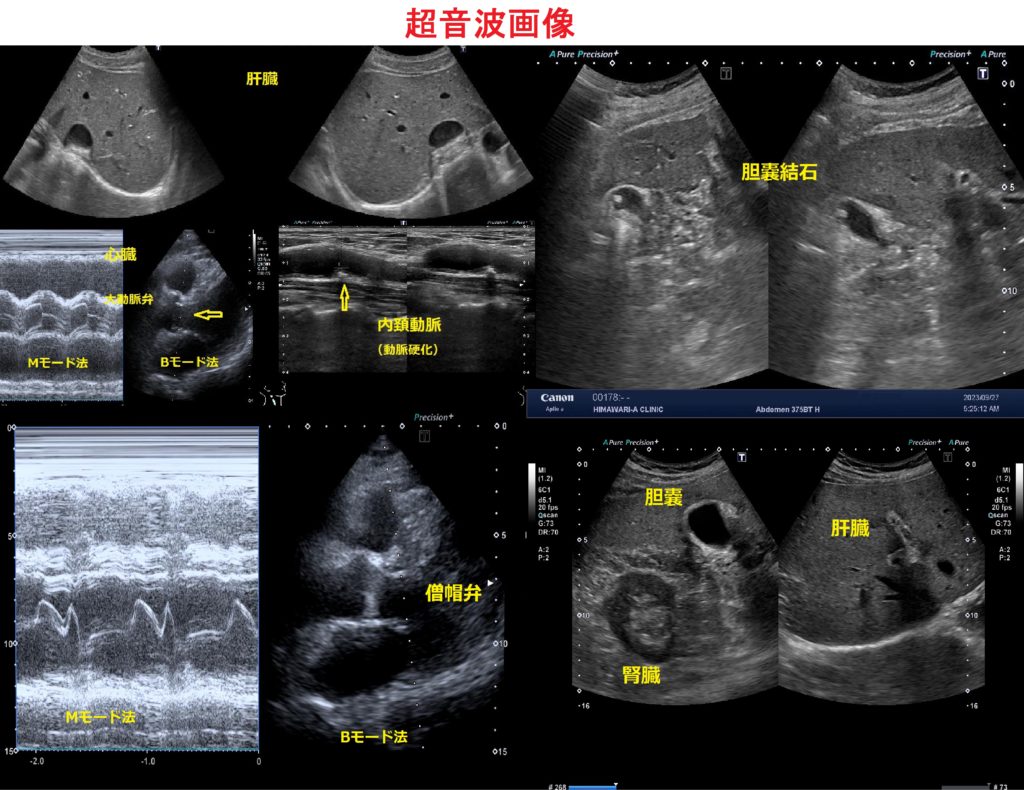

超音波画像診断装置

信号ノイズを低減し、解像度が非常に高いクリアな画像が映し出せるハイスペック機種です。設置されているクリニックは少なく、さらに疾患の病変が見つけやすくなり、 初期の段階で異常を発見できることが期待できます。

当院では、腹部、心臓、 乳腺、頸動脈の検査及び甲状腺、 泌尿器系等の検査受診が引き続き可能です。